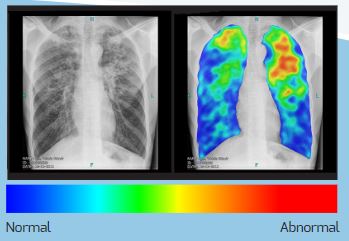

Le boîtier hors ligne CAD4TB est connecté à des systèmes radiologiques numériques validés pour recevoir des images radiologiques thoraciques postérieures - antérieures (PA). Le logiciel installé sur le boîtier analyse la radiographie du thorax en moins d'une minute. Le résultat est une carte thermique en couleur montrant les anomalies suspectes liées à la tuberculose, et un score entre 0 et 100 représentant la probabilité globale de tuberculose. Un score seuil est choisi pour déterminer quels patients doivent être orientés vers un test de suivi, tel que le GeneXpert, pour confirmer le diagnostic de TB. CAD4TB ne fournit pas d'informations sur les diagnostics non tuberculeux, dans de nombreuses situations, des lecteurs humains sont encore nécessaires pour examiner les radiographies pulmonaires.

Le logiciel de détection assistée par ordinateur (DAO) utilise des techniques d'intelligence artificielle (IA) et d'apprentissage profond pour analyser les images radiographiques thoraciques numériques (et non les films traditionnels) afin de détecter et de localiser les anomalies radiographiques suspectes. Ce logiciel est formé sur de grands ensembles de données (dans certains cas, des millions de radiographies thoraciques) et la qualité et la précision s'améliorent constamment. CAD4TB est l'un des logiciels de CAO utilisés spécifiquement pour détecter les anomalies associées à la tuberculose. Il a été démontré que ses performances sont comparables à celles des experts (radiologues). Le logiciel CAD a récemment été approuvé par l'OMS pour l'analyse numérique des radiographies pulmonaires pour le dépistage et le triage de la tuberculose chez les personnes âgées de 15 ans et plus.